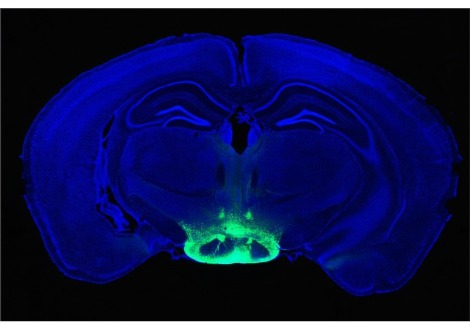

قام الباحثون أيضًا بفحص وفرة بروتينات الأميلويد في أدمغة المشاركين باستخدام تقنيات التصوير العصبي. يتراكم الأميلويد في الدماغ أثناء مرض الزهايمر ويُعتقد أنه يلعب دورًا في أعراضه الرئيسية ، بما في ذلك فقدان الذاكرة . وجد الباحثون أن حاملي APOE ε4 مع بعض تراكم الأميلويد لا يزالون يظهرون استرجاعًا أفضل للأشياء من غير الحاملين ، مما يشير إلى أن المتغير يمكن أن يكون وقائيًا في المراحل المبكرة من مرض الزهايمر. "من اللافت للنظر أن الميزة المعرفية  من وجود [ APOE ε4] يتم ملاحظتها حتى في وجود مرض الزهايمر" قال عالم النفس العصبي بجامعة جنوب كاليفورنيا ، ديوك هان ، والذي لم يشارك في الدراسة ، لمجلة Science .